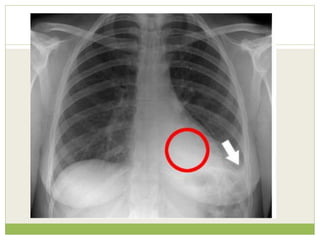

Findings

Left apical shadowing

Raised left hemidiaphragm

Increased extra-thoracic

soft tissue density (*) with

displacement of the

scapula on the left

(arrowheads) - compare

with right

๏‚— Interpretation in view of clinical details

๏‚— Cancer - Smoker with weight loss and left apical

consolidation/mass and no clinical features of

infection

๏‚— Phrenic nerve palsy - Increased shortness of

breath and raised left hemidiaphragm

๏‚— Brachial plexopathy - Arm pain and axillary soft

tissue swelling